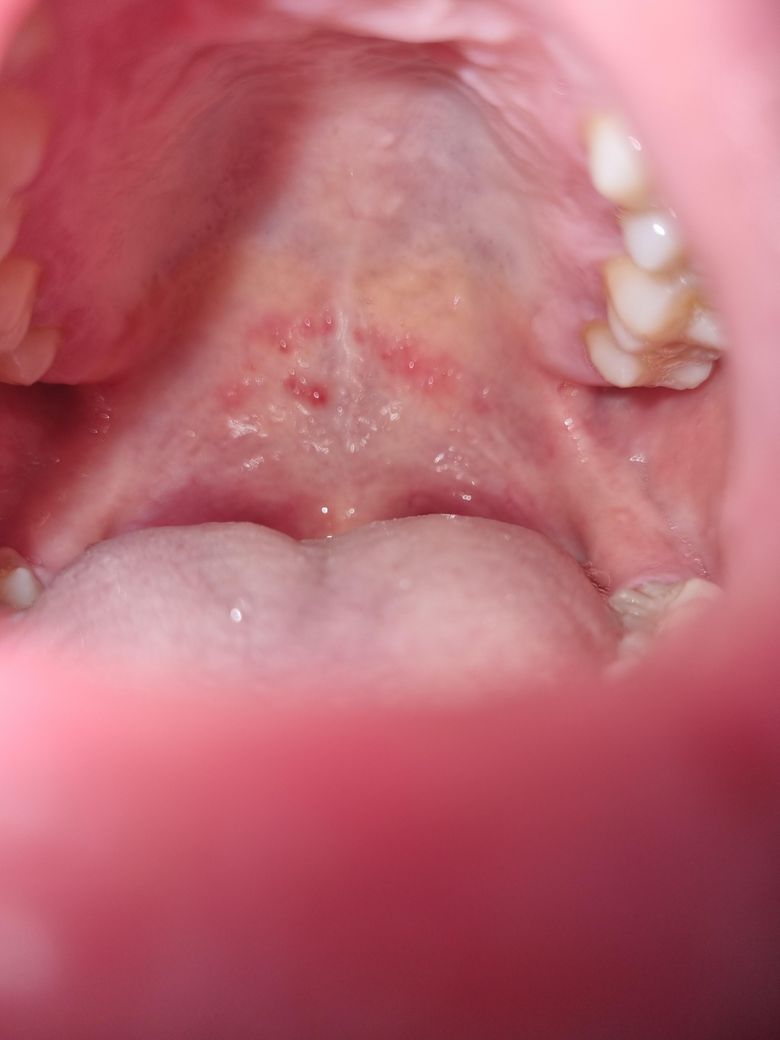

입천장 구내염발생 원인이 궁금합니다

관계 중 구강성교도 했는데 후에 1시간 후? 입천장에 이물감이 느껴졌고, 이상하게 여겨 보니까 수포같이 올라와 있었습니다.. 여러가지 알아보니까

헤르페스성 감염 (근데 입술말고 입천장만 수포)

등 인거같은데, 일단 저는 이물감이 있고 통증은 딱히 없으며 열도 없구요. 입안에 입천장 저기 말고는 따로 난곳이 없습니다 입술주변도 없음.

하지만 목이 답답한 느낌이들게 부어있어요.

토요일 관계직후 발생~ 현재 화요일 이네요 ㅜ 이비인후과 가보니 잘 모르겠다 하셔서요, 조직검사하기엔 돈이 없어서 증상과 사진으로 대충 알아보고싶습니다 ㅜㅜ

• 1번 째 사진